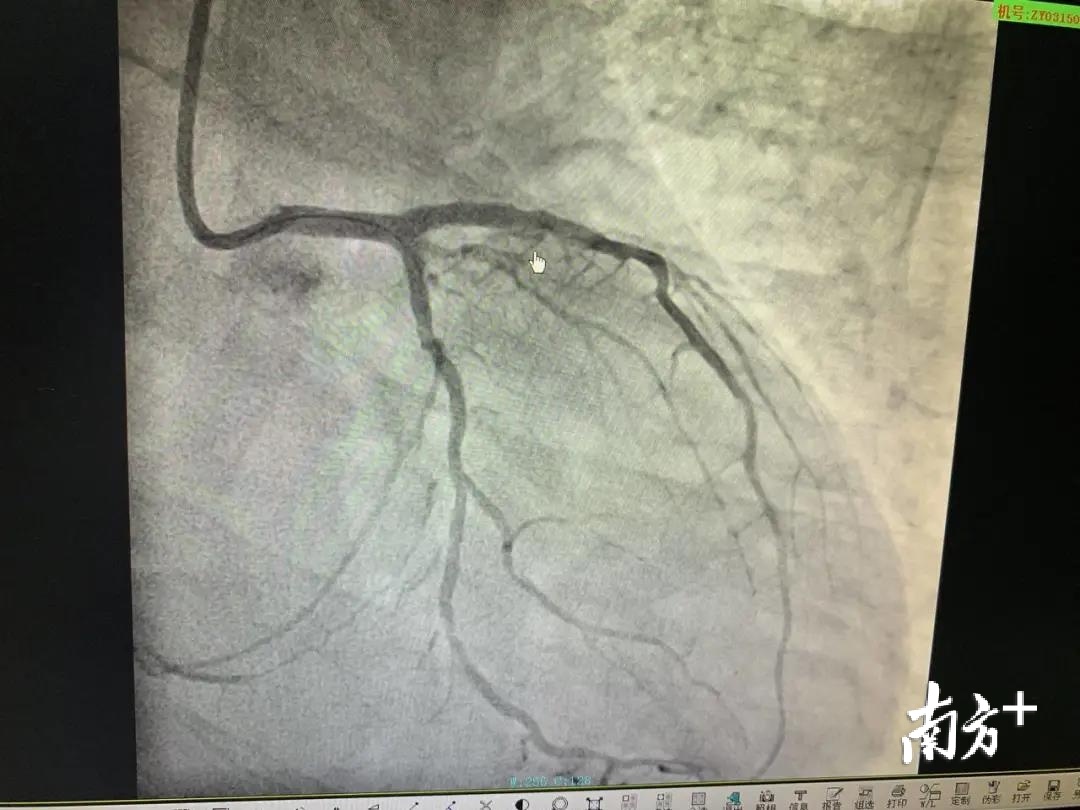

在完成左侧血管支架手术后,钱先生的病情得到了暂时缓解。但因右侧血管堵塞多时,不能正常供血,血管内已经严重钙化,出现了低血压、室速、心脏骤停的情况,被诊断为冠状动脉慢性完全闭塞性病变(CTO),这是冠脉介入治疗领域内难以攻克的堡垒。想要打通这条闭塞多时的血管,难度相当大。

兰军马上启动二次手术,尽早将闭塞的右侧血管打通。他采用目前世界最先进的“逆向导丝开通血管”技术。在距离第一场手术两周后,钱先生接受了第二场手术。在经过100分钟的奋战,心内科团队打通长期堵塞的右侧血管,成功地从死神手里夺回钱先生的生命。